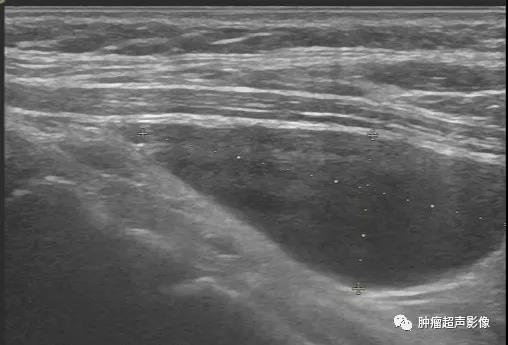

甲状腺左侧叶下极旁见边界清的无回声,椭圆形,与甲状腺组织之间有高回声包膜分隔,下极侧可见残留的高回声甲状旁腺(箭头示)从而确定甲状旁腺囊肿。